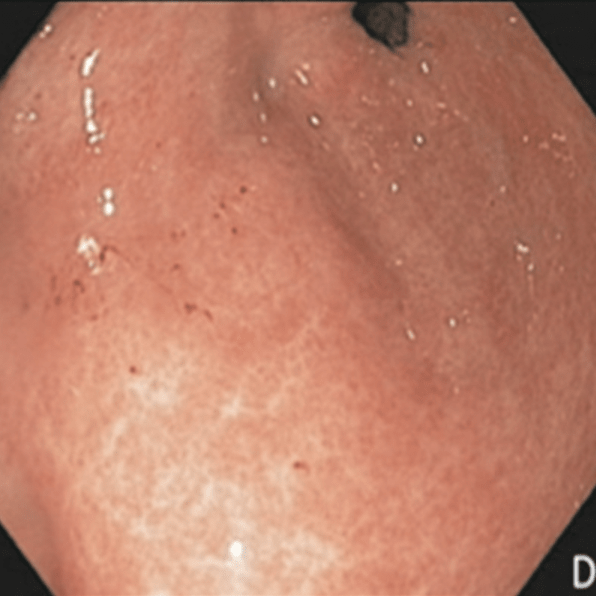

#EndoQuiz: Какой тип по Toljamo?

#EndoQuiz: Правильный ответ - Неполные эрозии (II тип), подтип IIa - плоские эрозии